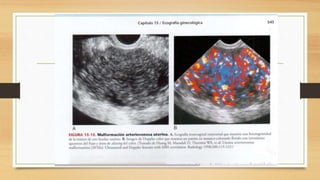

• Malformaciones arteriovenosas constan de un plexo vascular de arterias y venas sin

una red capilar intermedia

• Son lesiones raras que habitualmente afectan al miometrio y al endometrio.

• Pueden ser congénitas, la mayoría adquirida debido a traumatismo pélvico, una

cirugía y una neoplasia.

• Pacientes acuden con metrorragia y una reducción de la hemoglobina.

• El diagnostico es crítico debido a que una dilatación y legado puede provocar una

hemorragia catastrófica.

• En la ecografía las MAV pueden ser inespecíficas con mínimos singos.

Pueden verse como estructuras anecoicas y serpinginosas dentro de la pelvis

y pueden confundirse con quistes ováricos con múltiples cavidades, asas

intestinales llenas de liquiod e hidrosalpinx

• El Doppler color es diagnostico al demostras abundante flujo sanguíneo

dentro de las estructuras anecoicas